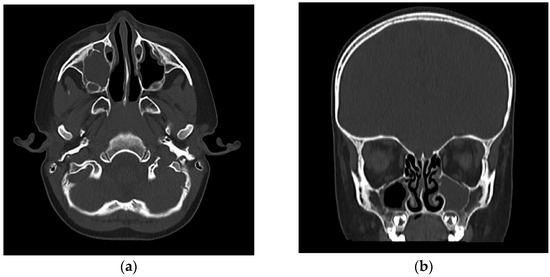

On clinical examination, the child presented with low-grade fever and irritability, with right superior and inferior palpebral edema, tenderness upon digital pressure over the maxillary sinus region, and minimal viscous mucopurulent discharge visible in the right nasal cavity originating from the middle nasal meatus. Nasal endoscopy confirmed the significant congestion and obstruction of the concerned middle meatus and the presence of discharge. Laboratory evaluation revealed leukocytosis with neutrophilia with a total white blood cell count of 19,800/mm3, elevated C-reactive protein levels (142 mg/L), and an erythrocyte sedimentation rate of 72 mm/h, all pointing to an acute bacterial infection. Given the atypical presentation, particularly in the absence of abundant nasal discharge, imaging was warranted to confirm the suspicion of sinusitis and assess for early orbital complications. A cranial computed tomography (CT) was performed, which showed complete opacification of the right maxillary sinus, with some mucosal thickening slightly extending into the adjacent ethmoid air cells but no evidence of abscess formation or orbital involvement (Figure 1).

Figure 1. (a) Axial view CT (bone window): complete opacification of the right maxillary sinus, showing no evidence of orbital or bony involvement. Subtle subcutaneous soft tissue thickening and increased density were noted over the right infraorbital region, suggestive of mild localized edema. (b) Coronal view CT (bone window): complete opacification of the right maxillary sinus. The right anterior ethmoid air cells showed mild mucosal thickening. The lamina papyracea and orbital floor were intact, with no radiological evidence of intraorbital extension or abscess formation. The coronal section confirms the blockage of the right osteomeatal complex.